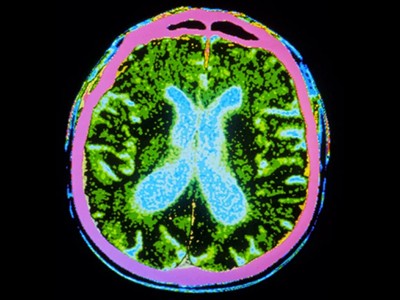

圖1:帕金森病的干細胞療法。

帕金森病是由于大腦中釋放多巴胺(多巴胺能)神經(jīng)元逐漸喪失所致。Sawamoto 等人1和 Tabar 等人2進(jìn)行了一項基于干細胞治療的臨床試驗。兩個(gè)團隊都使用了臨床級多能干細胞來(lái)補充多巴胺能神經(jīng)元,這種細胞可以無(wú)限分裂并分化為任何細胞類(lèi)型。Sawamoto等人使用了源自健康成年捐贈者細胞的誘導多能干細胞系,而Tabar等人使用了源自早期胚胎的人類(lèi)胚胎干細胞系。干細胞經(jīng)過(guò)培養,形成多巴胺能神經(jīng)元祖細胞。這些細胞被移植到稱(chēng)為殼核的大腦區域,殼核與尾狀核一起形成紋狀體。紋狀體與黑質(zhì)相連,而黑質(zhì)是多巴胺能神經(jīng)元損失最為嚴重的部位。早期(I/II期)臨床試驗主要證實(shí)了該療法的安全性,同時(shí)也表明其在改善癥狀方面具有一定有效性。